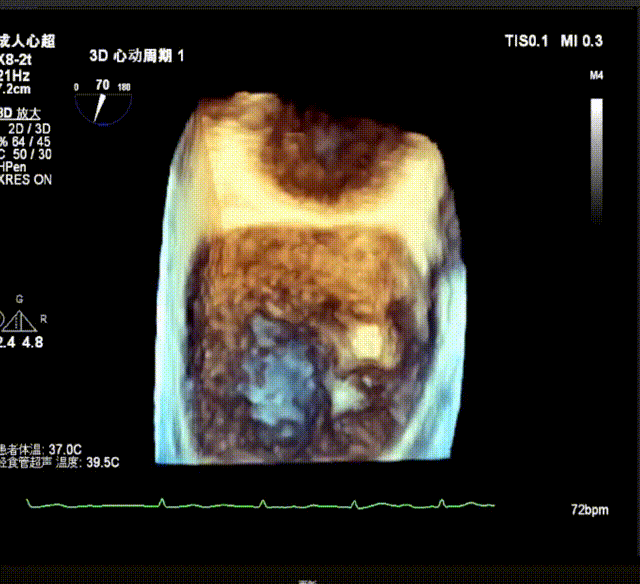

3D enface view示二尖瓣P2P3区瓣叶脱垂,偏心性返流

3D指示下调整瓣膜夹朝向病变区域P2偏P3区

确定瓣膜夹与病变区域垂直后,放下夹片,超声确认前叶后叶都夹合充分,3D检查瓣膜夹位置.